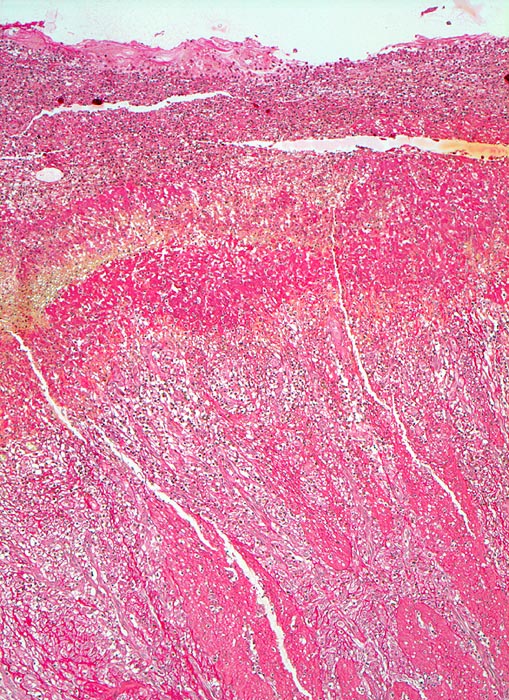

Das akute Ulkus ist rund, oval oder seltener polyzyklisch begrenzt und liegt meist im Schleimhautniveau. Das chronische Ulkus ist häufig kreisrund und im Längsschnitt trichter- oder treppenförmig. Die Schleimhautränder können lippenförmig über den Ulkusgrund hinausragen. Palpatorisch ist das chronische Ulkus aufgrund der narbigen Fibrose induriert. Die Schleimhautfalten laufen sternförmig auf das Ulkuszentrum zu. Das chronische Ulkus tritt zu 10%, das akute zu 25% multipel auf. Mikroskopisch zeigt das chronische Ulkus eine typische Schichtung (s. Bilder). Die Gefässe im Ulkusgrund zeigen eine starke Intimaproliferation mit teilweiser oder vollständiger Obliteration der Gefässlichtung. Morphologische Veränderungen in der übrigen Magenschleimhaut geben einen Hinweis auf die Ätiologie des Ulkus (Typ B oder C Gastritis).